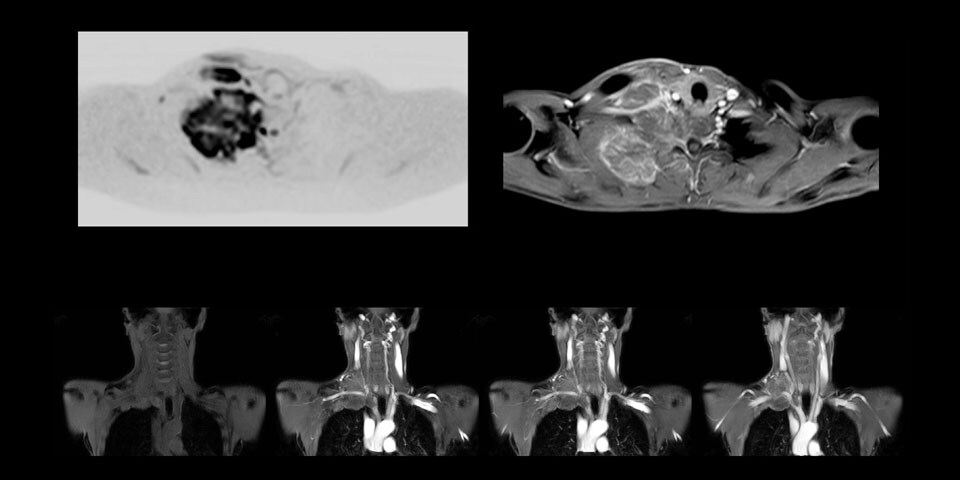

A 61-year-old female with a malignant lymphoma underwent an MRI exam with whole body diffusion weighted imaging (DWIBS) as well as PET. On the images shown, the resolution of DWIBS is better than PET, which allows visualization of the small pelvic lesions and almost no distortion is seen in the neck area.